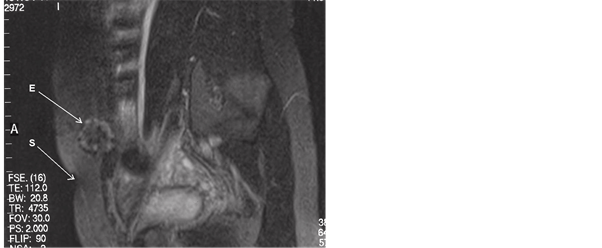

Blood sample demonstrated normal values, apart from slightly elevated levels of CA 125 (36.5 U/ml ) and CA 19.9 (40.3 U/ml). Ultrasound scan and X-ray had negative or aspecific features. Magnetic resonance imaging gave more interesting patterns, showing the localization of the nodule, involving the deep layers of the abdominal wall ( muscles and fascia, see Figure 2), and the distance from the laparotomic scar (Figure 3).

Figure 2. RMI transverse abdominal scan: the deep abdominal wall mass is evidenced (arrows) on the left paramedian side. E = endometrioma, S= Pfannenstiel’s laparotomic scar.

Figure 3. RMI, longitudinal paramedian scan: the distance between the endometrioma (E) and the Pfannenstiel’s laparotomic scar (S) of the caesarean section can be seen.